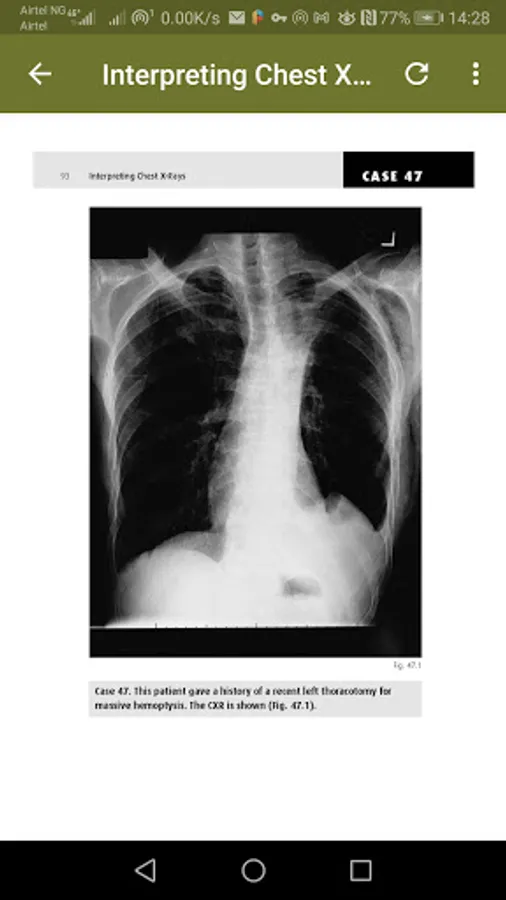

The chest radiography is a very commonly requested examination and it is probably the hardest plain film to interpret correctly. It is, however, often performed out of hours with interpretation undertaken by relatively junior members of staff, frequently with no senior radio-logical advice available. All the X-rays are accompanied by a simple line diagram outlining where the abnormality is.